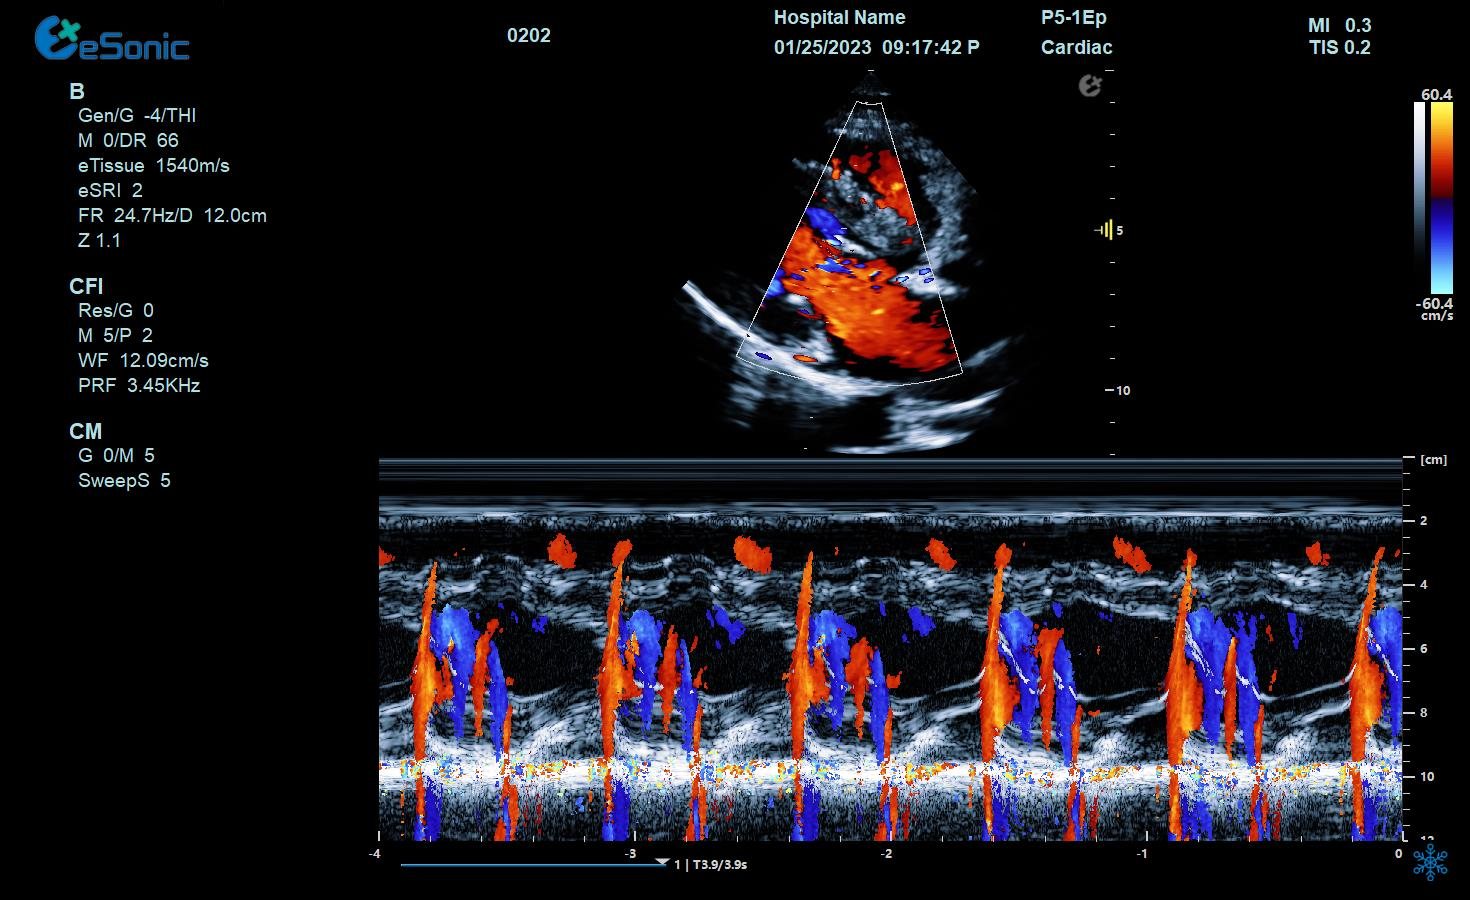

临床病例(二)

男性,82岁,临床诊断:风心病 房颤

超声表现:左房大,二尖瓣增厚、回声增强、运动僵硬;CDFI显示二尖瓣、三尖瓣、主动脉瓣返流信号。

风心瓣膜病二、三尖瓣关闭不全

相关心脏应用功能--M型、解剖M型

相关心脏应用功能--M型、解剖M型技术总结:

彩色M型:

直观显示室璧运动和血流动力学关系。

更精准判断血流时向,更精准评估心脏功能。